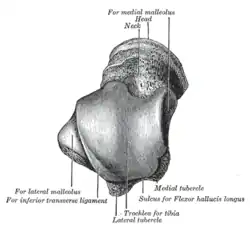

The body features several prominent articulate surfaces: On its superior side is the trochlea tali, which is semi-cylindrical,[6] and it is flanked by the articulate facets for the two malleoli.[3] The ankle mortise, the fork-like structure of the malleoli, holds these three articulate surfaces in a steady grip, which guarantees the stability of the ankle joint. However, because the trochlea is wider in front than at the back (approximately 5–6 mm) the stability in the joint vary with the position of the foot: with the foot dorsiflexed (toes pulled upward) the ligaments of the joint are kept stretched, which guarantees the stability of the joint; but with the foot plantarflexed (as when standing on the toes) the narrower width of the trochlea causes the stability to decrease.[7] Behind the trochlea is a posterior process with a medial and a lateral tubercle separated by a groove for the tendon of the flexor hallucis longus. Exceptionally, the lateral of these tubercles forms an independent bone called os trigonum or accessory talus; it may represent the tarsale proximale intermedium. On the bone's inferior side, three articular surfaces serve for the articulation with the calcaneus, and several variously developed articular surfaces exist for the articulation with ligaments.[3]

The head of talus looks forward and medialward; its anterior articular or navicular surface is large, oval, and convex. Its inferior surface has two facets, which are best seen in the fresh condition.[8]

The medial, situated in front of the middle calcaneal facet, is convex, triangular, or semi-oval in shape, and rests on the plantar calcaneonavicular ligament; the lateral, named the anterior calcaneal articular surface, is somewhat flattened, and articulates with the facet on the upper surface of the anterior part of the calcaneus.[8]

The body of the talus comprises most of the volume of the talus bone (ankle bone). It presents with five surfaces; a superior, inferior, medial, lateral and a posterior:[8]

- The superior surface of the body presents, behind, a smooth trochlear surface, the trochlea, for articulation with the tibia. The trochlea is broader in front than behind, convex from before backward, slightly concave from side to side: in front it is continuous with the upper surface of the neck of the bone.

- the inferior surface presents two articular areas, the posterior and middle calcaneal surfaces, separated from one another by a deep groove, the sulcus tali. The groove runs obliquely forward and lateralward, becoming gradually broader and deeper in front: in the articulated foot it lies above a similar groove upon the upper surface of the calcaneus, and forms, with it, a canal (sinus tarsi) filled up in the fresh state by the interosseous talocalcaneal ligament. The posterior calcaneal articular surface is large and of an oval or oblong form. It articulates with the corresponding facet on the upper surface of the calcaneus, and is deeply concave in the direction of its long axis which runs forward and lateralward at an angle of about 45° with the median plane of the body. The middle calcaneal articular surface is small, oval in form and slightly convex; it articulates with the upper surface of the sustentaculum tali of the calcaneus.

- The medial surface presents at its upper part a pear-shaped articular facet for the medial malleolus, continuous above with the trochlea; below the articular surface is a rough depression for the attachment of the deep portion of the deltoid ligament of the ankle-joint.

- The lateral surface carries a large triangular facet, concave from above downward, for articulation with the lateral malleolus; its anterior half is continuous above with the trochlea; and in front of it is a rough depression for the attachment of the anterior talofibular ligament. Between the posterior half of the lateral border of the trochlea and the posterior part of the base of the fibular articular surface is a triangular facet which comes into contact with the transverse inferior tibiofibular ligament during flexion of the ankle-joint; below the base of this facet is a groove which affords attachment to the posterior talofibular ligament.

- The posterior surface is narrow, and traversed by a groove running obliquely downward and medialward, and transmitting the tendon of the Flexor hallucis longus. Lateral to the groove is a prominent tubercle, the posterior process, to which the posterior talofibular ligament is attached; this process is sometimes separated from the rest of the talus, and is then known as the os trigonum. Medial to the groove is a second smaller tubercle.